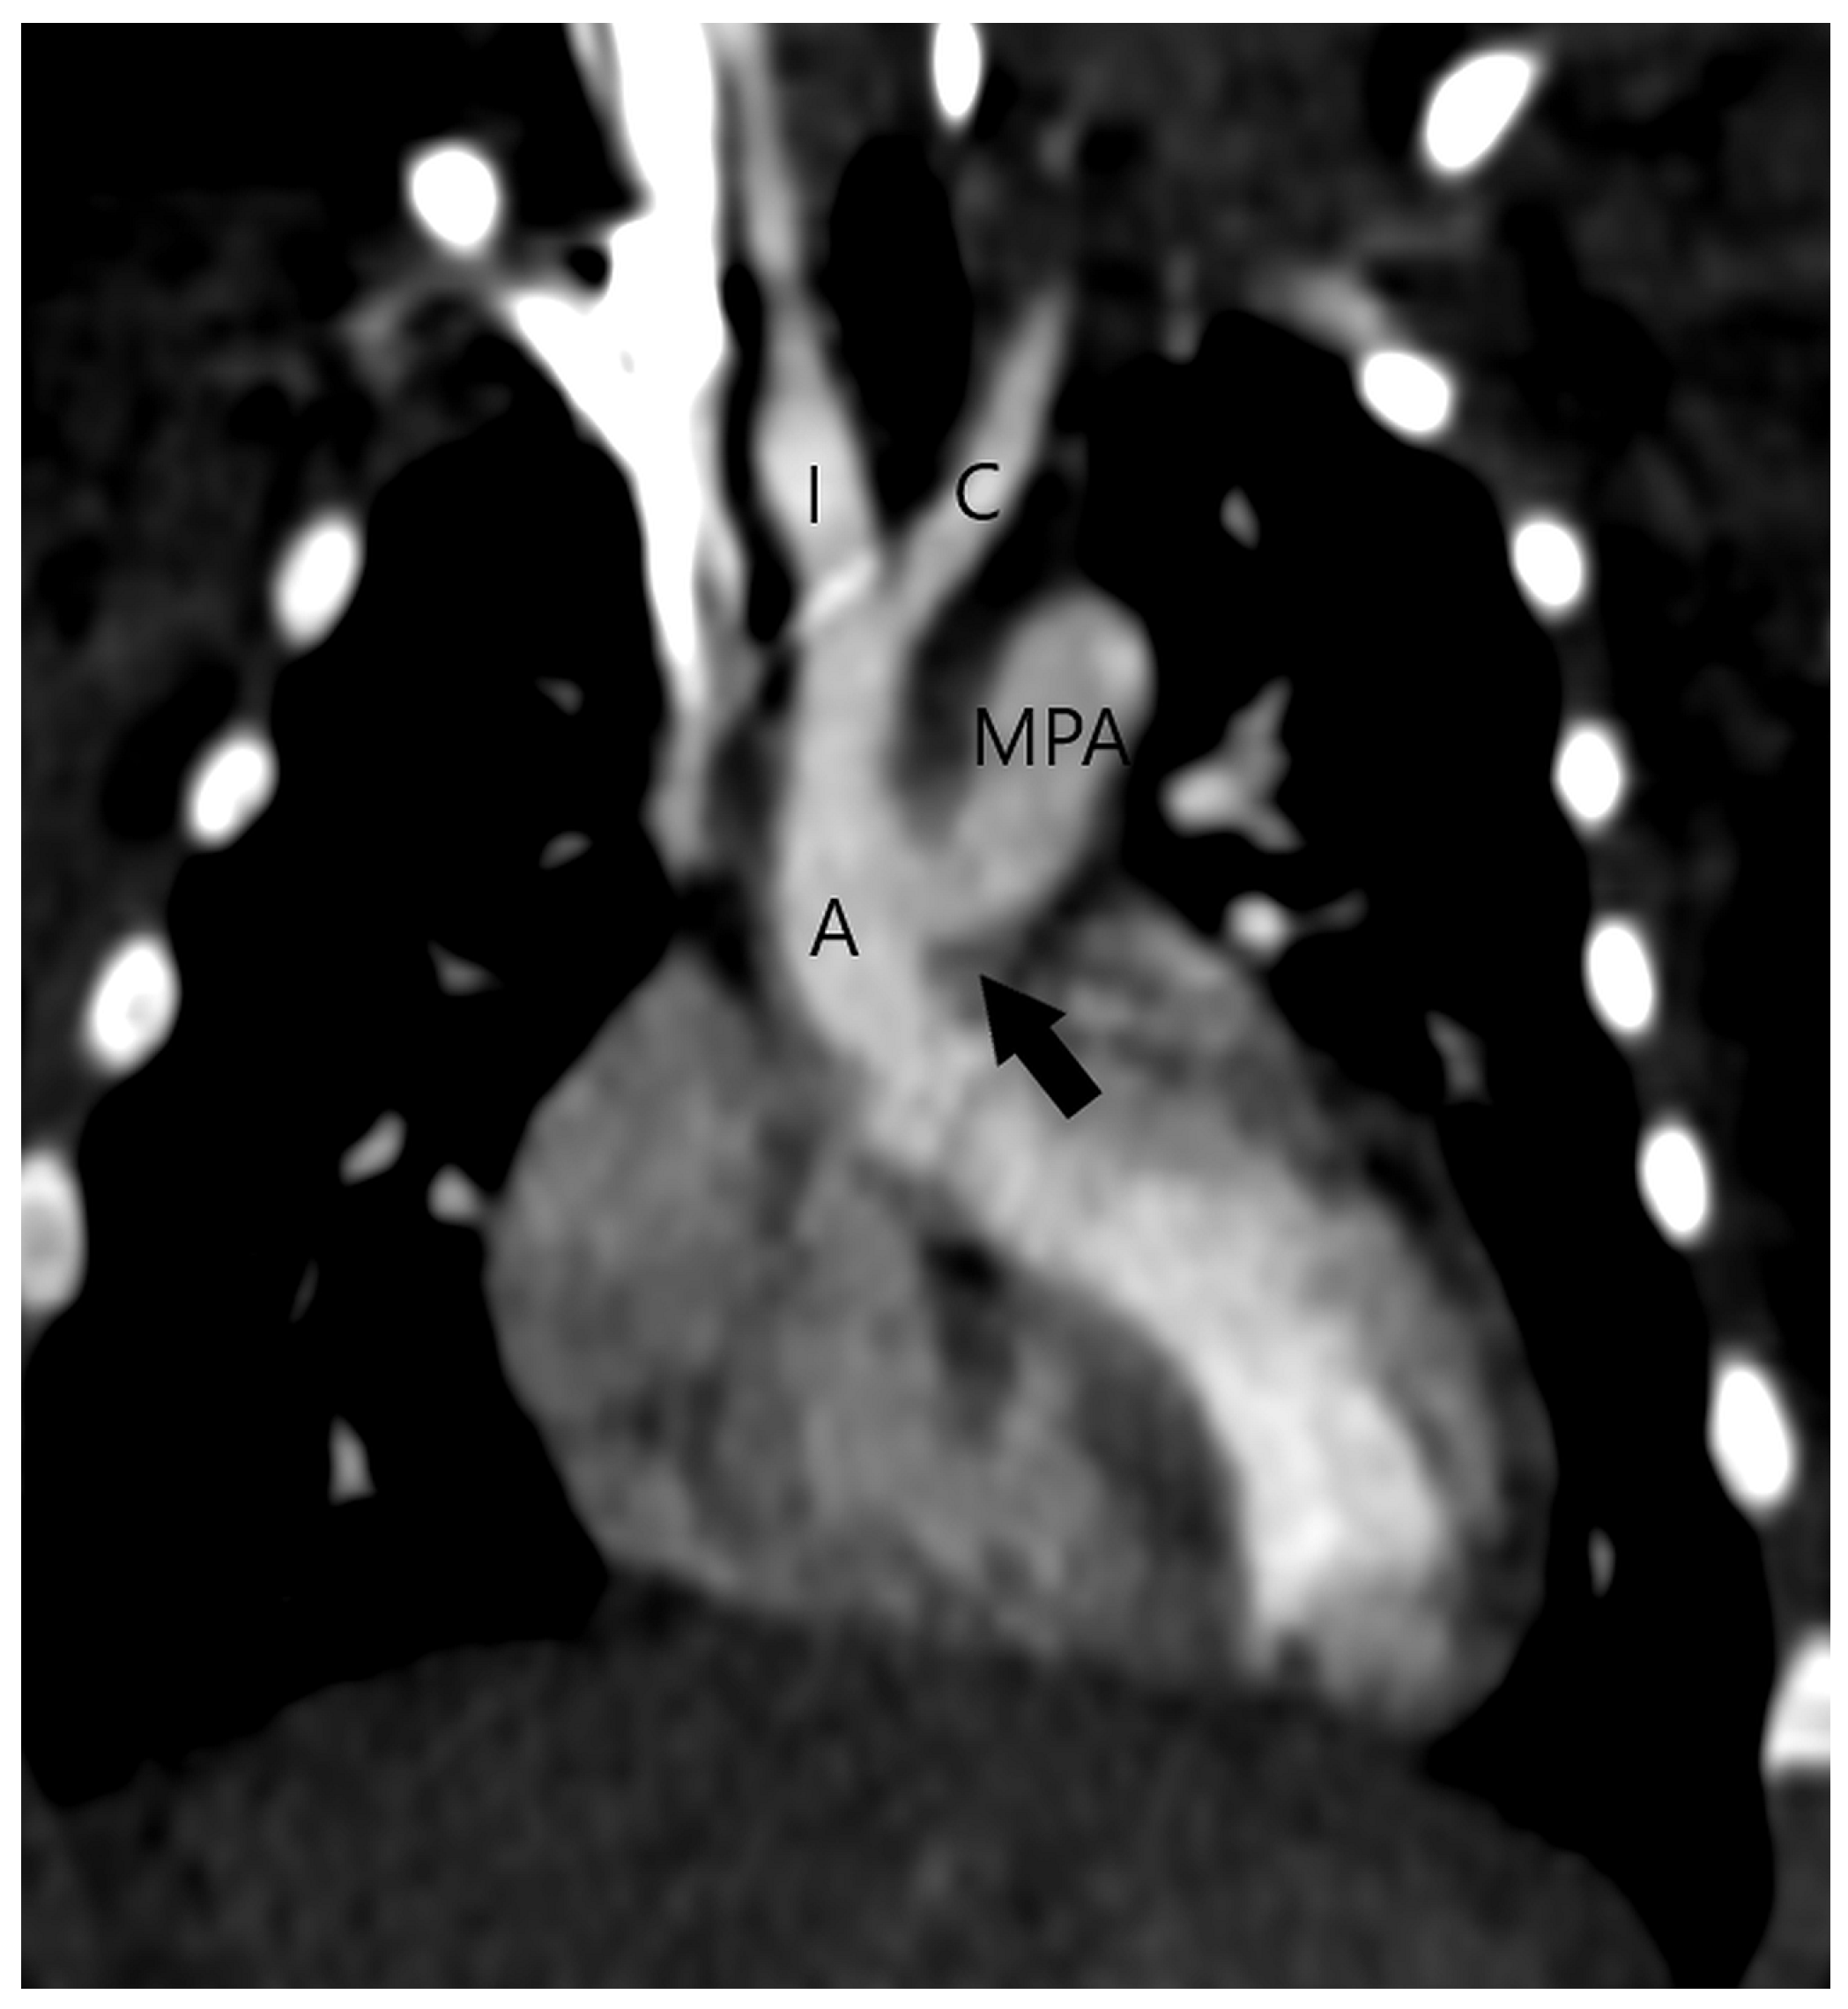

The aortopulmonary septal defect is located between the semilunar valves and the branch pulmonary arteries. If an APW is identified on CT, its type should be determined. Type 1 or (Figure 2) Type 2 APW is located between the distal part of the ascending aorta and the anterior wall of the origin of the right pulmonary artery (Figure 3), whereas type 3 is a total defect that involves the entire aortopulmonary septum or ascending aorta [1]. Type 4 or an intermediate type has similar features to the total defect but has adequate superior and inferior rims and is most suited for device closure [1]. Table 1 summarizes key points in the CT evaluation of patients with an aortopulmonary window.

Figure 2.

Type 1 or proximal type of aortopulmonary septal defect (arrow) is located just above the semilunar valve between the ascending aorta (A) and the right wall of the main pulmonary artery (MPA) (A). The right-sided aortic arch can also be detected. After surgery, the ascending aorta (A) and the main pulmonary artery (MPA) are separated (B).